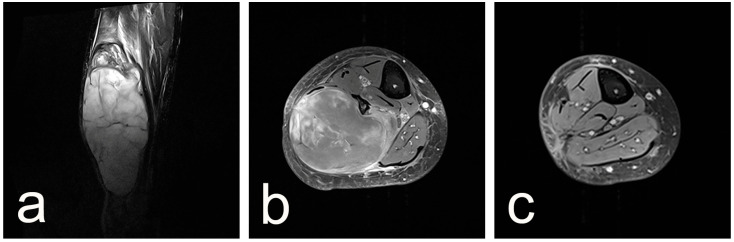

Background and Clinical Significance: Neurofibromatosis type 1 (NF1) predisposes individuals to various peripheral nerve sheath tumors (PNSTs), including benign neurofibromas, malignant peripheral nerve sheath tumors (MPNSTs), and intermediate lesions known as atypical neurofibromatous neoplasms of uncertain biologic potential (ANNUBP), previously often termed atypical neurofibroma. These atypical lesions are considered premalignant precursors to MPNST. Case Presentation: We present the case of a 33-year-old male with NF1 who developed a rapidly growing, painful mass in his right calf. Clinical examination revealed signs consistent with NF1. Magnetic resonance imaging showed a large, heterogeneous mass in the lateral compartment. Biopsy revealed a neurofibroma with hypercellularity, moderate atypia, scarce S100 positivity, focal CD34 positivity, and an elevated Ki-67 proliferation index of 10-12%, consistent with ANNUBP. The patient underwent wide surgical resection, including the fibula and peroneal muscles. At the 30-month follow-up, there was no local recurrence, though the patient had a mild residual limp. Discussion: This case highlights the clinical presentation, diagnostic features, and management considerations for ANNUBP in NF1, emphasizing the importance of recognizing warning signs and the role of pathology in guiding treatment for these high-risk precursor lesions.